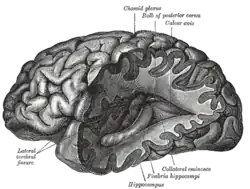

- Lesions – A classic method in which a brain-region of interest is naturally or intentionally destroyed to observe any resulting changes such as degraded or enhanced performance on some behavioral measure. Lesions can be placed with relatively high accuracy "Thanks to a variety of brain 'atlases' which provide a map of brain regions in 3-dimensional "stereotactic coordinates.